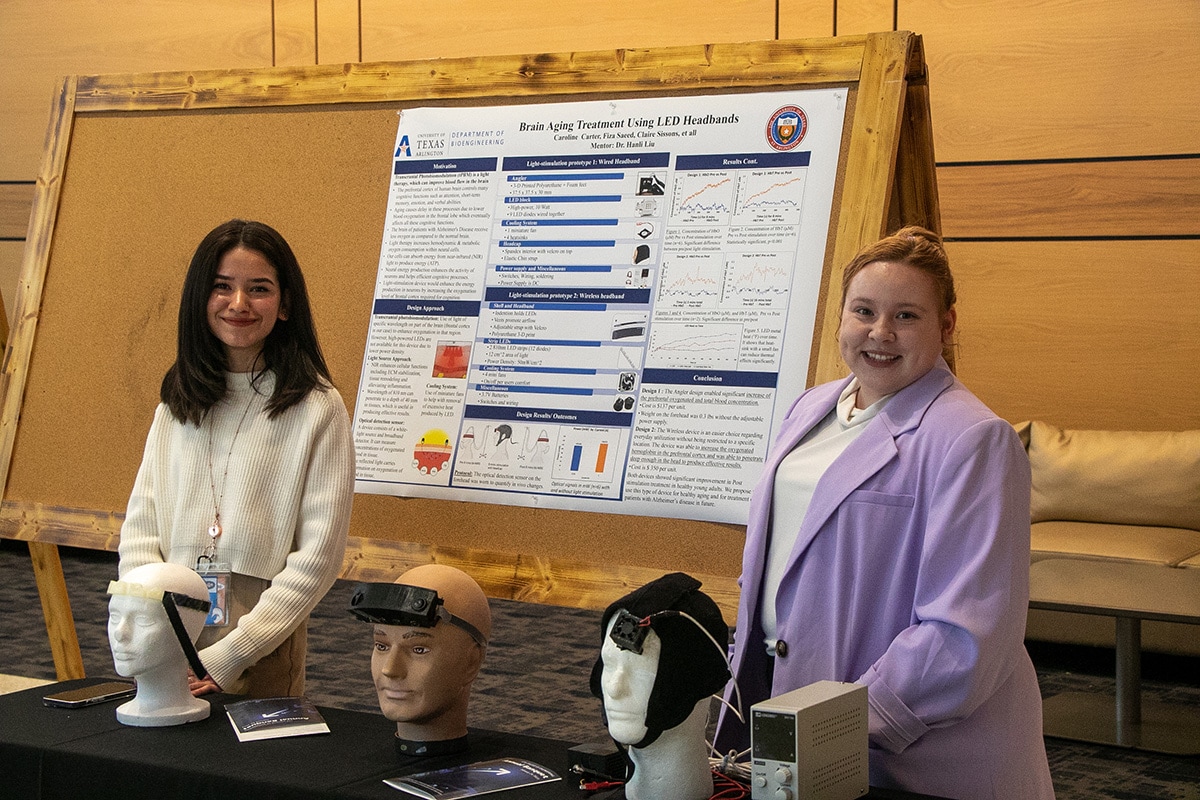

Innovation Day

Innovation Day celebrates and showcases the innovative, transformative research and undergraduate capstone projects being done by College of Engineering students. Community members and industry leaders are invited to participate and observe the depth and breadth of research occurring in UTA's College of Engineering. Mouser is excited to sponsor the annual Innovation Day event.